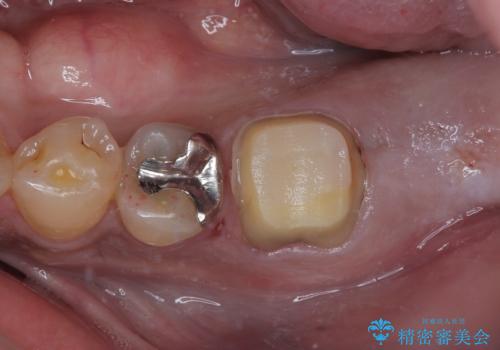

- 食事などで噛んだ時に奥歯が痛むとのことで来院された患者様です。

レントゲン写真より、一番奥の歯の根尖部に大きな病変(炎症により骨が溶けている状態)が認められたため、根管治療を行うこととしました。

歯根が破折した歯は抜歯となるため、抜歯して病変の部分に骨が回復するのを待って、インプラントによる補綴治療を行うこととしました。